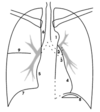

On a Posterior-Anterior CXR, the normal right heart and mediastinal border are made up of four structures. Name them from the bottom to the top.

* Inferior Vena Cava (bottom) * Right Atrium * Ascending Aorta * Superior Vena Cava (top)

On a Posterior-Anterior CXR, the normal left heart and mediastinal border comprise five structures. Name them from the bottom to the top.

* Left Ventricle (bottom) * Left Atrium * Pulmonary Artery * Aortic Arch * Subclavian Artery/Vein (top)